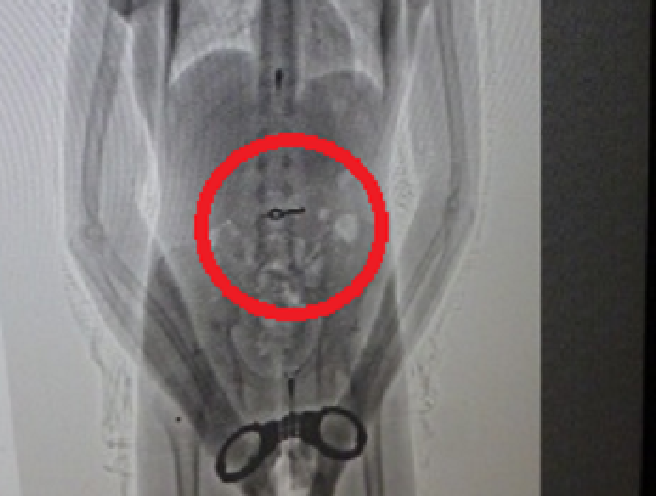

SCOPERTO CON UNA RADIOGRAFIA

Magazine 1 di 1 © Dal Web Uruguay, un insolito piano di fuga: detenuto mangia la chiave delle manette 1 di 1 Avvia slideshow © Dal Web SCOPERTO CON UNA RADIOGRAFIA Uruguay, un insolito piano di fuga: detenuto mangia la chiave delle manette 06 nov 2013 - 08:02 1 foto SCOPERTO CON UNA RADIOGRAFIA uruguay ICONA DI STILE Nuovo Ducati Monster, rivoluzione naked: più leggero, veloce e tecnologico Facile da ricordare e da usare Il numero dell’energia: arriva il 140 per l’assistenza clienti AVVENTURA SENZA LIMITI Dalla città all'off-road: Ford Ranger è il pick-up che porta la famiglia ovunque Cinque secoli di tradizione Cotechino Modena IGP: il "re della tavola” non va in letargo dopo Capodanno progettare il futuro Mobilità sostenibile e biocarburanti, ripensare trasporti e logistica UNA MINACCIA INVISIBILE RAEE, così i rifiuti elettronici avvelenano i suoli italiani: solo 4 su 10 sono gestiti correttamente